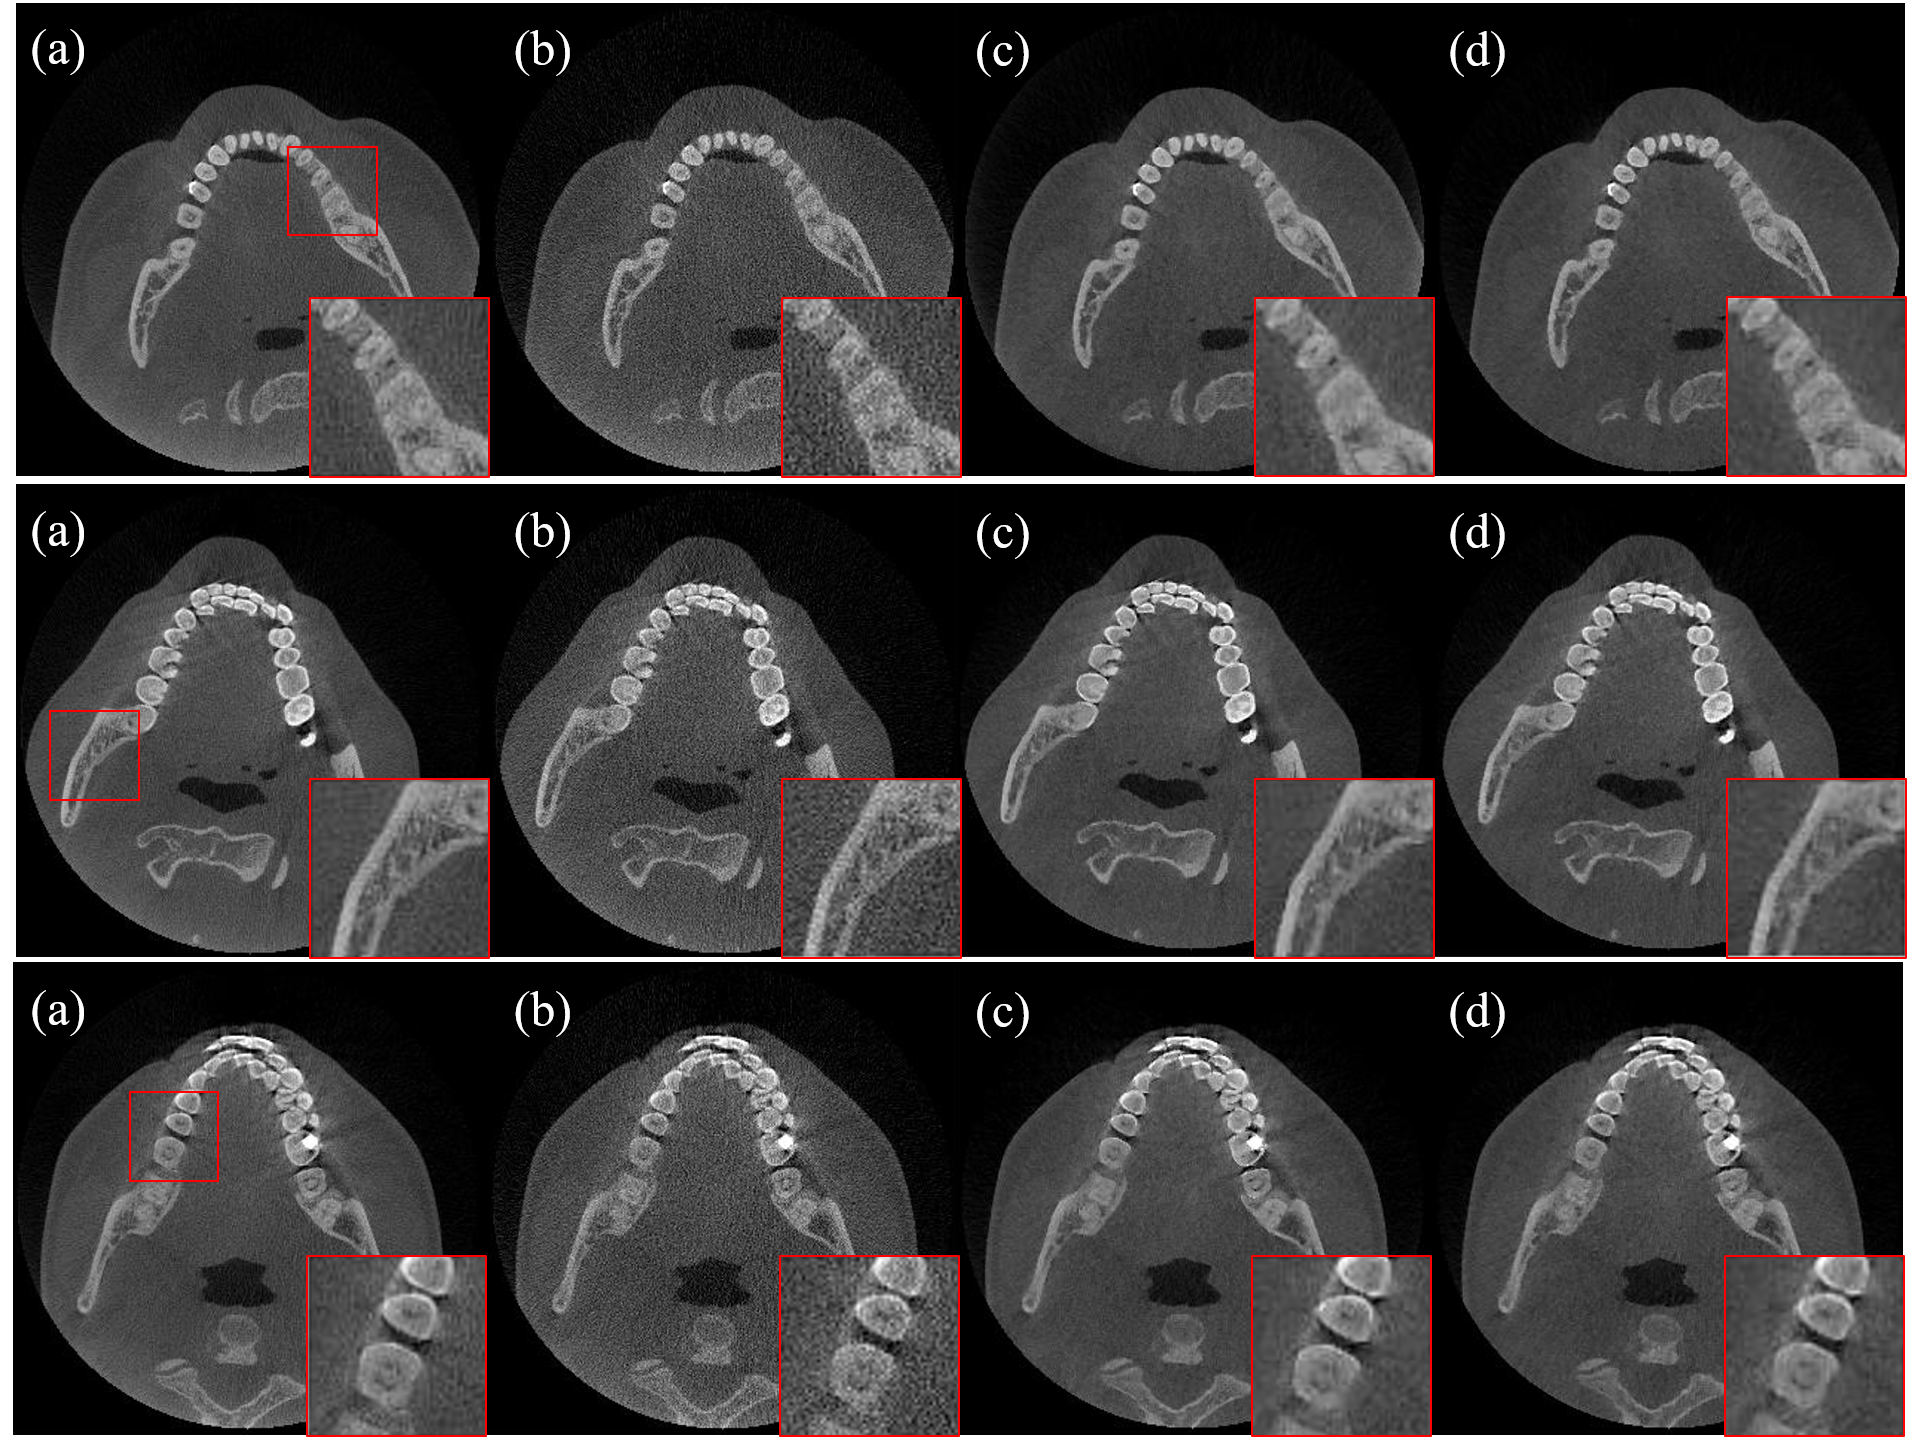

In Fig.2, ground-truth, LDCT FBP reconstruction, NLM-WLS iterative reconstruction, and MBDL network reconstruction were displayed for visual comparison. Details denoted by red boxes were zoomed-in and displayed in the lower left corner. As shown in Fig.2, the noise was well suppressed in both iterative reconstruction and MBDL reconstruction, the details of teeth and bone were restored to a large extent as in zoomed-in.